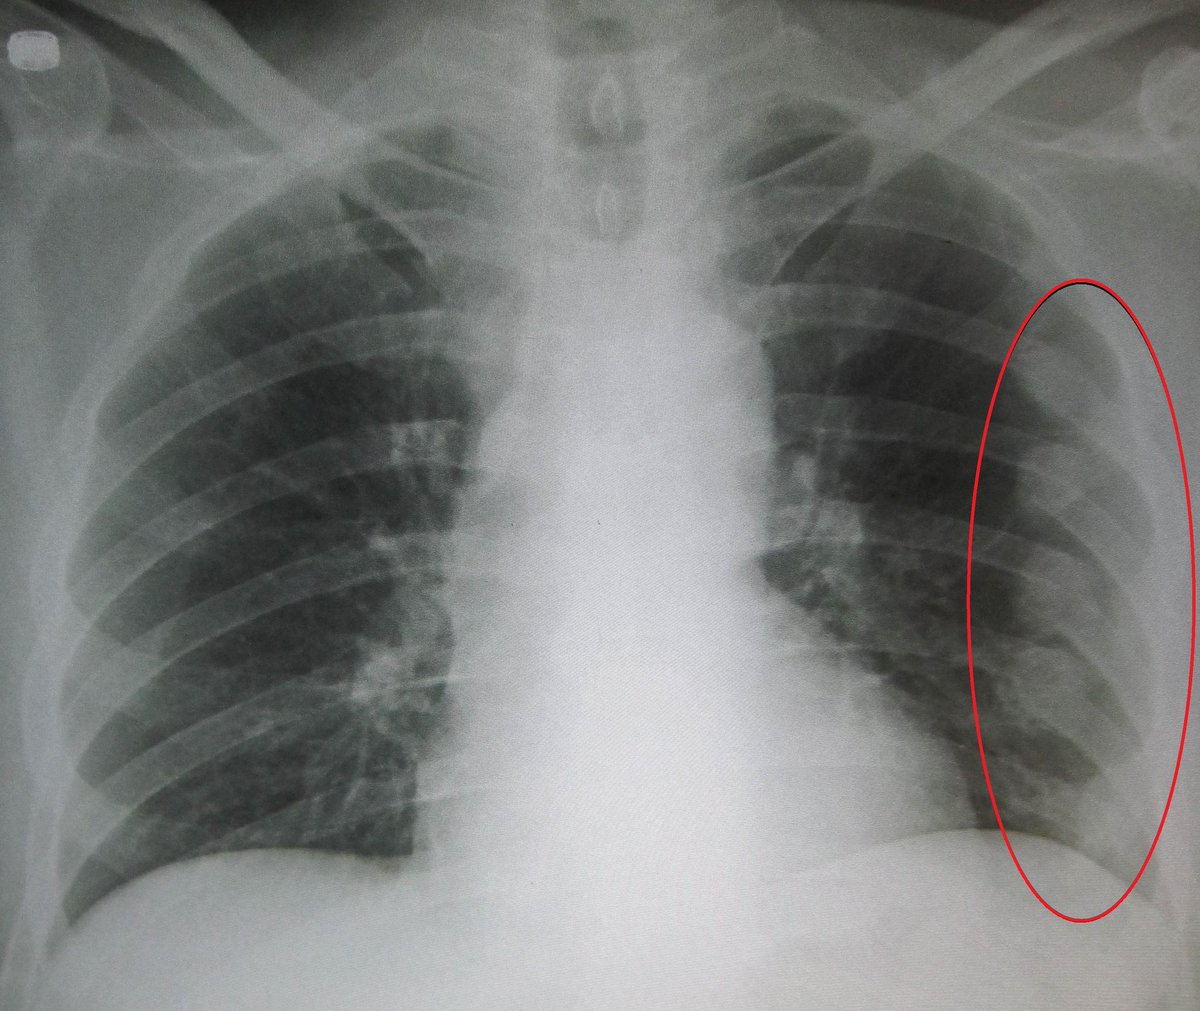

٣/ كسور الاضلاع: جراح الصدر هو المسؤول عن علاجها ومتابعتها ومايصاحبها من إصابات في الصدر.